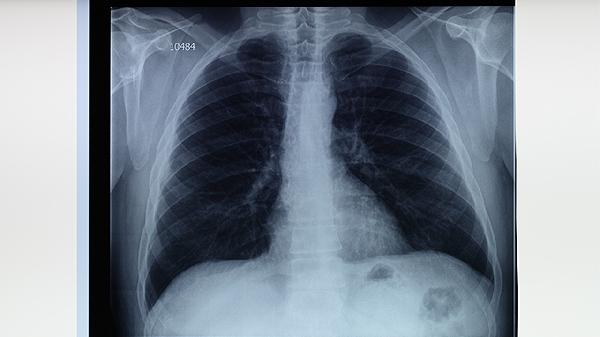

需同时满足痰培养结核分枝杆菌阳性,且药敏试验显示对异烟肼和利福平耐药。分子检测如GeneXpert MTB/RIF可快速识别利福平耐药,但完整耐药谱仍需传统培养法确认。影像学可见空洞型病变或多肺叶浸润更常见。

加强结核病患者治疗管理,确保规范完成6-8个月标准疗程。接触者应定期进行胸部X线筛查,高危人群可预防性使用左氧氟沙星。医疗机构需落实感染控制措施,对痰涂片阳性患者实施呼吸道隔离。